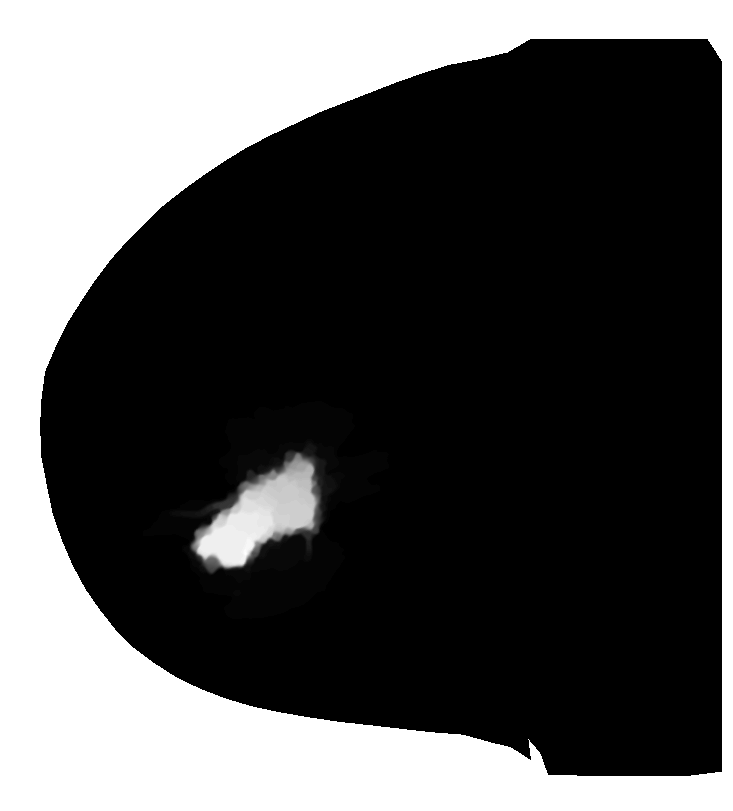

First we will use a Magnetic Resonance (MR) image of a female breast, taken from eby2008magnetic with permission from111www.slicer.org, to segment the tumor mass. On the top/right of Fig. 4, we see the first eigenfunction segmenting the tumor perfectly out of the breast image. Next, in the middle row of Fig. 4, we add to the image , of standard Gaussian noise, such that

| (15) |

where is i.i.d. Gaussian random variable with mean zero, variance equal to one and represents the noise level. Now, we compute the adaptive eigenspace of . Again, the first eigenfunction holds a nice segmentation of the tumor despite the additional noise. To demonstrate the quality of our approach, we consider the image but this time we destroy the boundaries of the tumor and change them by blurring (using an image manipulation program). The resulting image is shown on the bottom left of Fig. 4. On the bottom right of Fig. 4, we see the segmentation is accurate and captures the tumor and its blurred boundaries.

To reduce computational cost and get even more accurate results, we may create a Finite Element (FE) grid on the area of interest rather than on the image boundaries. For illustration, we consider the MR-images and shown on the top/left and bottom/left of Fig. 4, respectively. We automatically produce a mesh on the breast boundaries (see on the left of Fig. 5). The segmentation for and for is shown on the center and right of Fig. 5, respectively.